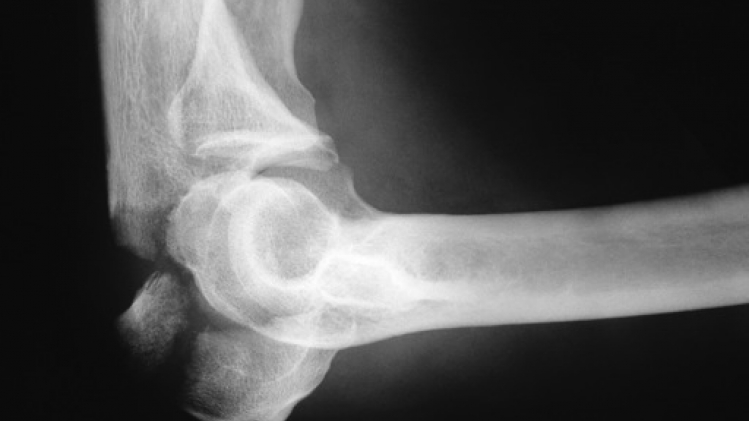

Une prothèse partielle du coude a été posée sur un patient vendredi à l'hôpital Jan Yperman d'Ypres. Il s'agit d'une opération habituellement effectuée sur les patients souffrant d'arthrose de la partie externe du coude, une maladie plus rare que l'arthrose de la hanche ou du genou, mais particulièrement douloureuse. La procédure a été effectuée en compagnie du Dr. Pooly, le concepteur de la prothèse, venu de Newcastle (Royaume-Uni) pour l'occasion.

En Belgique, cet hôpital est le seul à pratiquer cette opération pour le moment. Une prothèse partielle permet, selon l'hôpital, de s'assurer que "seule la partie endommagée du coude est remplacée, l'articulation elle-même restant intacte", ce qui permet un rétablissement bien plus rapide du patient.